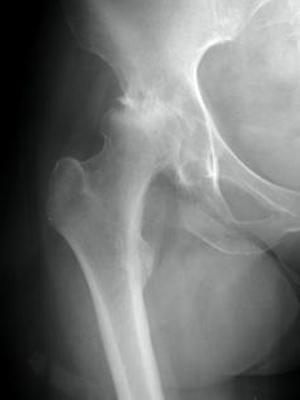

Принято считать, что ожирение повышает риск развития остеоартрита. В связи с этим, если вы предпримете шаги по снижению веса, вы также уменьшите количество изменений, связанных с развитием или обострением остеоартрита. Если у вас остеоартрит в одном из суставов, несущих нагрузку, например, в колене или бедре, потеря веса улучшит вашу способность к реабилитации после операции на суставе.